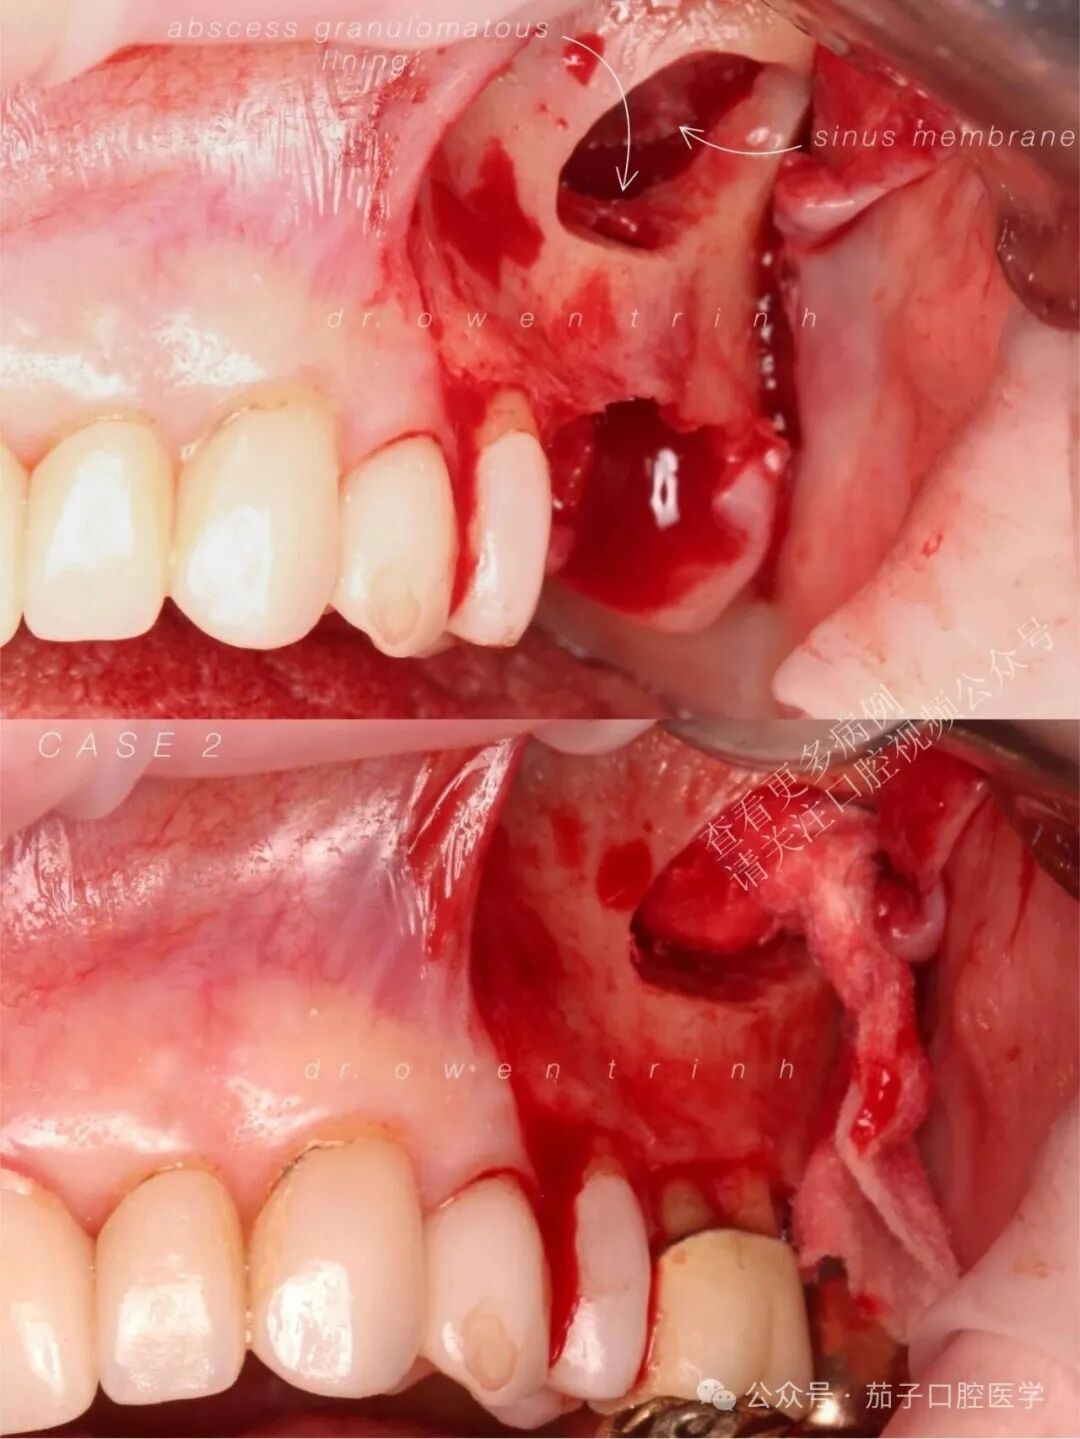

如果不将上颌窦黏膜从脓肿周围的肉芽肿组织上剥离,直接进行拔牙和彻底的根尖刮治,极易导致上颌窦黏膜撕裂。这不仅会造成术中并发症,还可能使后续为种植做准备的上颌窦增量(垂直骨再生)手术变得更加困难。

实际情况

由于增厚的上颌窦黏膜(慢性上颌窦炎)与脓肿之间存在强烈的粘连/附着,上颌窦黏膜很难与根尖牙槽骨壁分离(在抬升黏膜时阻力极大),这与气化良好的上颌窦底黏膜截然不同。此外,由于缺乏气化的牙槽突骨质,使得抬升上颌窦黏膜变得困难,因为医生必须使用上颌窦刮匙在14号牙和15号牙根尖牙槽骨的每一个转角和曲度中进行操作。